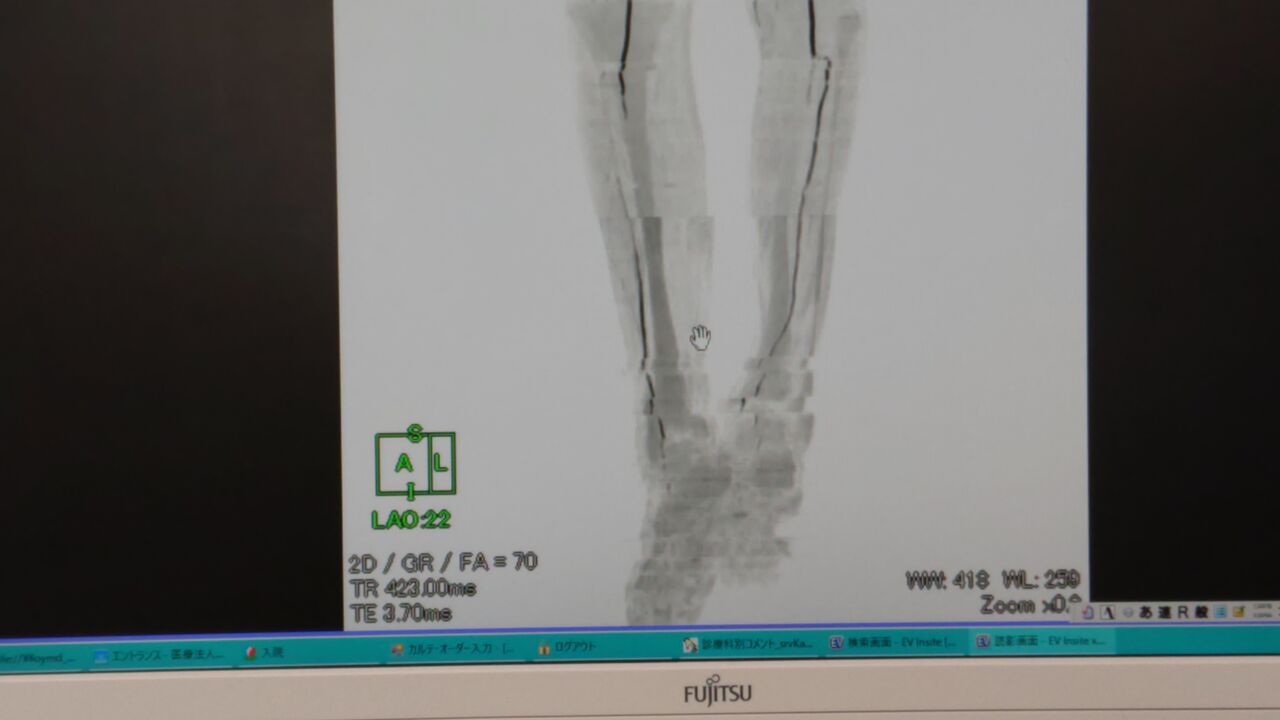

腰から膝までの血管に異常はない

膝から下の血管は細く、

指先まで途中で途切れた状態

レントゲンの写真(医師の許可あり)

この画像は足の後ろだと思いますが、

前からの画像は、ほぼ、血管は真っ白な状態でした

この状態で、足の指を切断しても、

血が流れていないので、治癒できないとの事